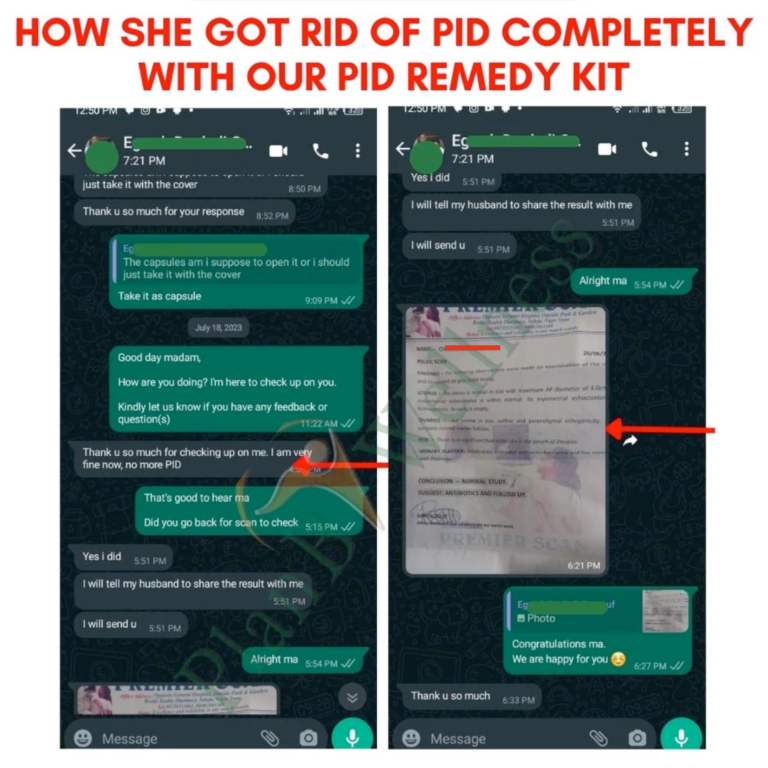

Our Happy Customers Who Love The PID Remedy Kit

Real Reviews From Real People

Our Happy Customers Who Love The PID Remedy Kit

Real Reviews From Real People

Support & Follow-Up with a Dedicated Health Advisor

You’re not just buying a product; you’re gaining a partner in your healing journey.

With this bonus, you’ll be assigned a dedicated Health Advisor who will guide you step-by-step via WhatsApp or phone call.

From tracking your progress to answering your private questions, you will have expert support anytime you need it.

We will monitor your improvement to ensure the infection is gone for good.

You never have to walk this road alone again.